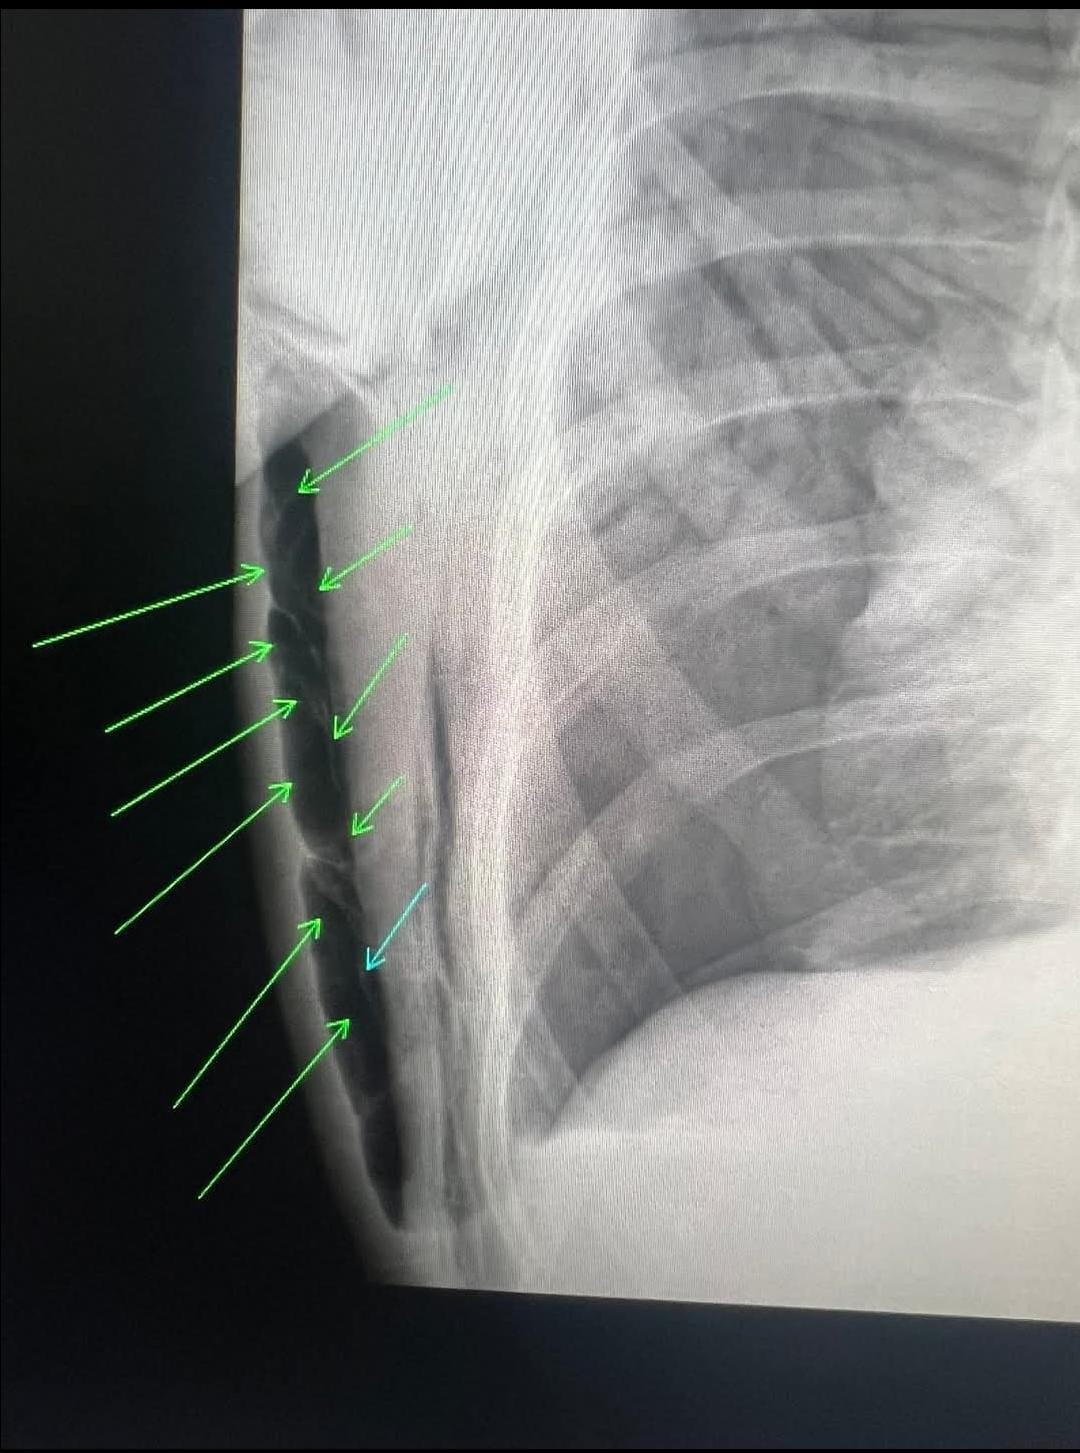

“Nəfəs aldığı hava plevra boşluğuna daxil olub ağciyəri sıxıb büzüşdürüb-total kollaps (spontan tension pnevmotoraks) olub. Sağ plevra boşluğundakı havanın çıxması üçün bülau drenajı qoyulub, fəqət drenajın plevra boşluğundakı hissəsi qatlanıb oradakı havanın çıxmasına mane olub. Deşilmiş ağciyərdən plevra boşluğuna daxil olan havanın təzyiqi artaraq bu dəfə drenaj dəliyindən döş qəfəsi divarındakı dəlikdən yumşaq toxumalar arasına daxil olaraq dərialtı emfizema-subcutaneous emphysema yaradıb”.

Həkimin paylaşdığı görüntüləri təqdim edirik: